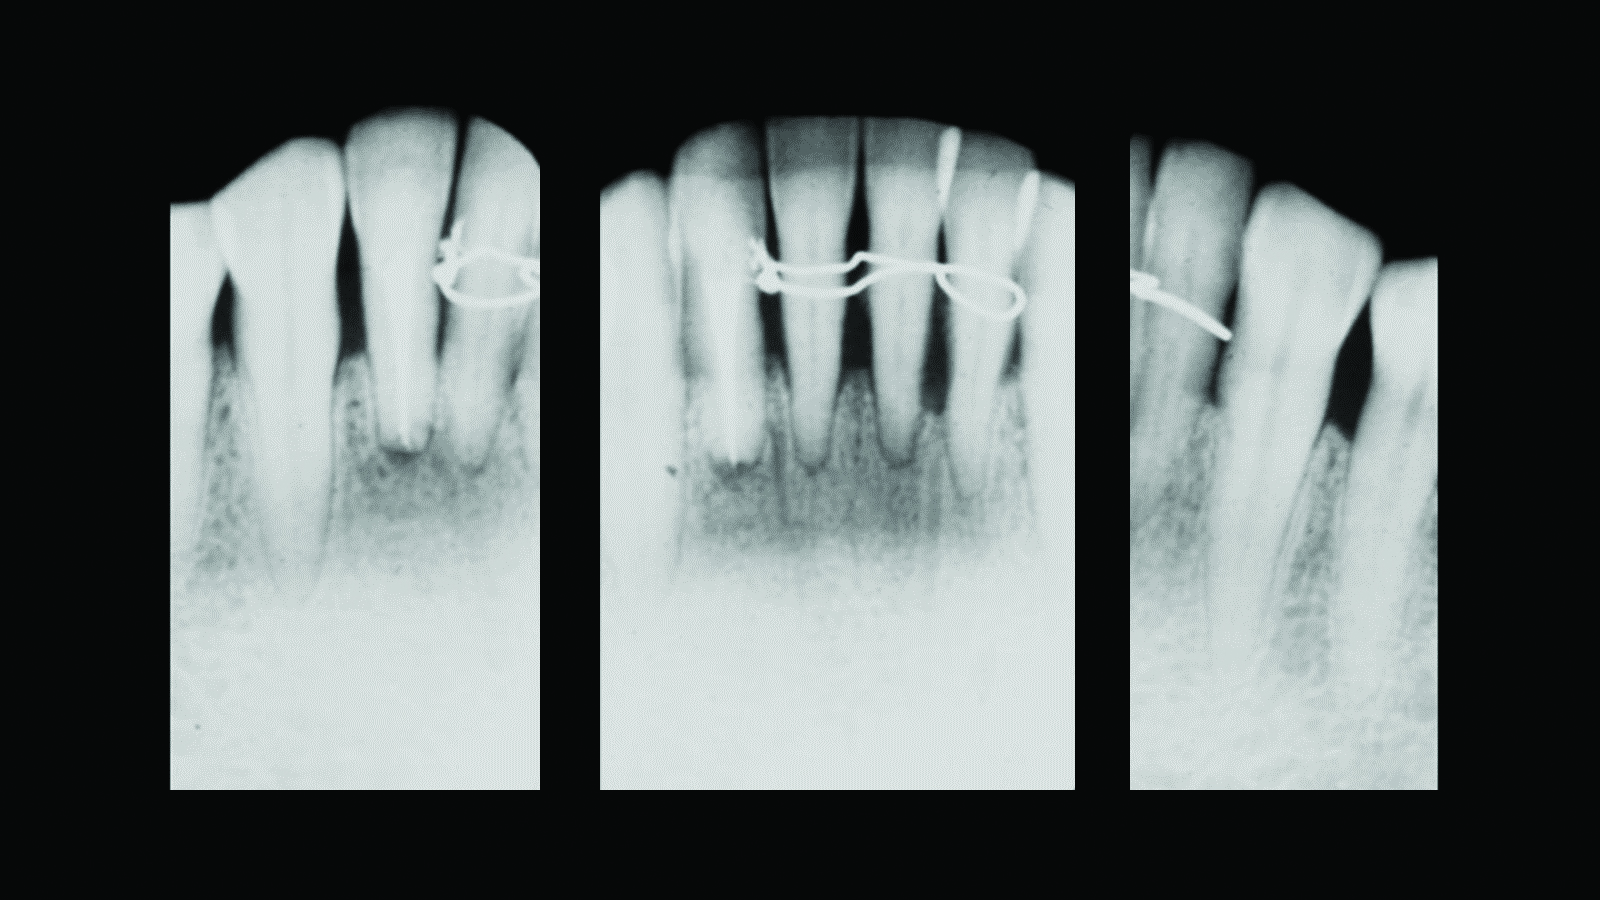

Fig 7. Case 2. Initial presentation of a patient with periodontitis (teeth Nos. 22 through 27). Generalized pocket depths of 6 mm to 7 mm were present, with wire splint on teeth Nos. 23 through 25.

Figure 7

Fig 8. Initial radiograph of the Case 2 patient, teeth Nos. 22 through 27. Fig 9. SRP resulted in the elimination of inflammation and remaining probing depths of 2 mm to 3 mm in Case 2 patient, 3 months post-therapy. (Fig 4 through Fig 9 are courtesy of Dennis Tarnow, DDS.)

Figure 8

Fig 9. SRP resulted in the elimination of inflammation and remaining probing

depths of 2 mm to 3 mm in Case 2 patient, 3 months post-therapy.

(Fig 4 through Fig 9 are courtesy of Dennis Tarnow, DDS.)